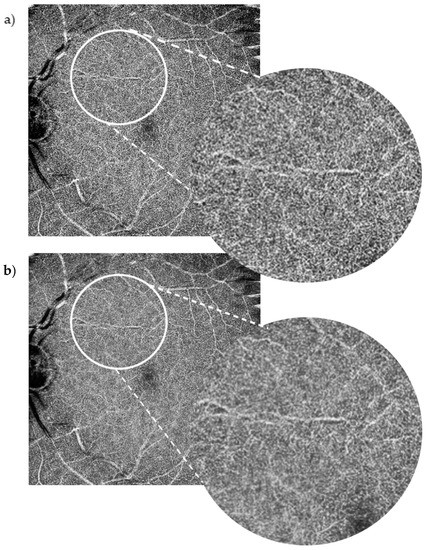

Figure 2.

10 × 10 mm OCT-A scan of the deep capillary plexus. Baseline image (a) vs. denoised image (b). The positive impact of the denoise software on the Superficial Capillary Plexus (SCP) did not apply to the same extent to the Deep Capillary Plexus (DCP). Although the more clinically standard smaller field DCP scans were of higher quality, the widefield 10 × 10 mm images for this study showed shadowing from the SCP and relative loss of clarity.